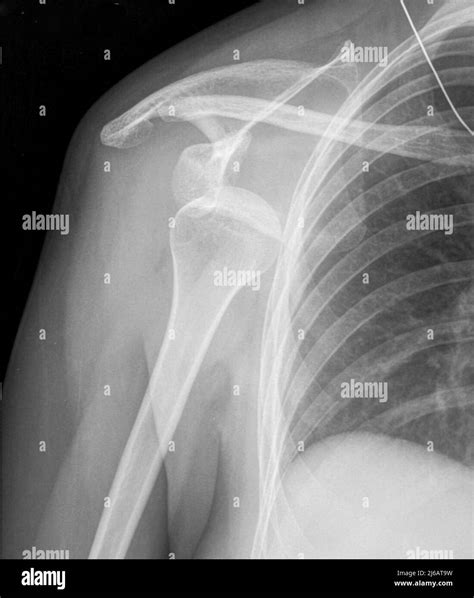

Experiencing a sudden, sharp pain in your shoulder after a fall or a sports-related impact is a distressing ordeal. Often, the first thing medical professionals will order to assess the situation is a Dislocated Shoulder X Ray. Understanding why this imaging is critical, what it reveals, and how it guides your recovery journey is essential for anyone dealing with this common orthopedic injury. A dislocated shoulder occurs when the ball of your upper arm bone (the humerus) pops out of the shoulder socket (the glenoid). Because this area is complex, precise imaging is the gold standard for confirming the diagnosis and ruling out associated complications.

• Visualizing the position of the bones: It confirms whether the humerus is truly out of the socket or if there is a partial dislocation (subluxation).

• Assessing alignment: It helps doctors identify the specific type of dislocation—whether it is anterior (forward), posterior (backward), or inferior (downward).

Typically, the technician will request at least two or three different views of the shoulder to ensure a comprehensive diagnosis:

• Anteroposterior (AP) View: Taken from the front, this view helps doctors see the general relationship between the humerus and the socket.

• Axillary View: This view captures the shoulder from underneath, which is crucial for identifying if the bone has moved forward or backward.

• Scapular Y View: This provides a lateral perspective, allowing the radiologist to see if the humeral head is centered in the socket of the scapula.